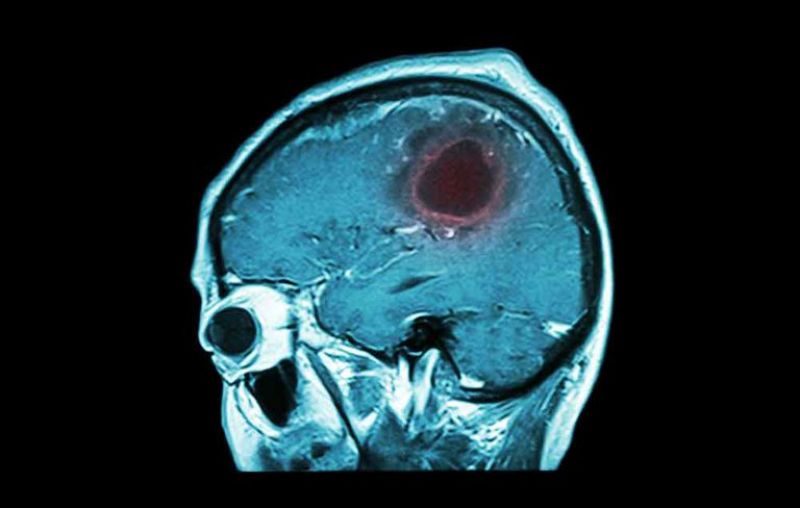

ਬ੍ਰੇਨ ਟਿਊਮਰ ਦਾ ਪਤਾ ਲਗਾਉਣ ਲਈ ਸੱਭ ਤੋਂ ਪਹਿਲਾਂ ਸਰੀਰਕ ਪ੍ਰੀਖਣ ਕੀਤਾ ਜਾਂਦਾ ਹੈ ਜਿਸ ਦੇ ਤਹਿਤ ਦਿਮਾਗੀ ਪ੍ਰਣਾਲੀ ਦਾ ਫੈਲਾਅ ਪ੍ਰੀਖਖ ਕੀਤਾ ਜਾਂਦਾ ਹੈ। ਡਾਕਟਰ ਇਹ ਦੇਖਣ ਲਈ ਇਕ ਪ੍ਰੀਖਣ ਕਰਦੇ ਹਨ ਕਿ ਕਰੈਨਿਅਲ ਨਰਵ ਠੀਕ ਹਨ ਜਾਂ ਨਹੀਂ। ਇਹੀ ਉਹ ਨਰਵ ਹਨ ਜੋ ਤੁਹਾਡੇ ਦਿਮਾਗ ਤੋਂ ਪੈਦਾ ਹੁੰਦੀਆਂ ਹਨ। ਸਰੀਰਕ ਪ੍ਰੀਖਣ ਤੋਂ ਬਾਅਦ ਰੋਗ ਦਾ ਪਤਾ ਚਲਦਾ ਹੈ। ਸੀਟੀ ਸਕੈਨ, ਐਮ.ਆਰ.ਆਈ, ਏਜੀਓਗ੍ਰਾਫ਼ੀ ਜਾਂ ਸਿਰ ਦੀ ਬਾਇਓਪਸੀ ਕੀਤੀ ਜਾ ਸਕਦੀ ਹੈ।